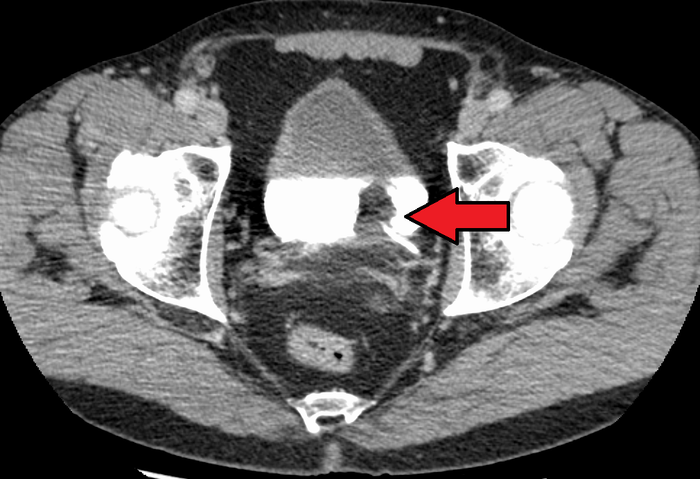

Hình ảnh CT San ung thư bàng quang. Ảnh: Sưu tầm